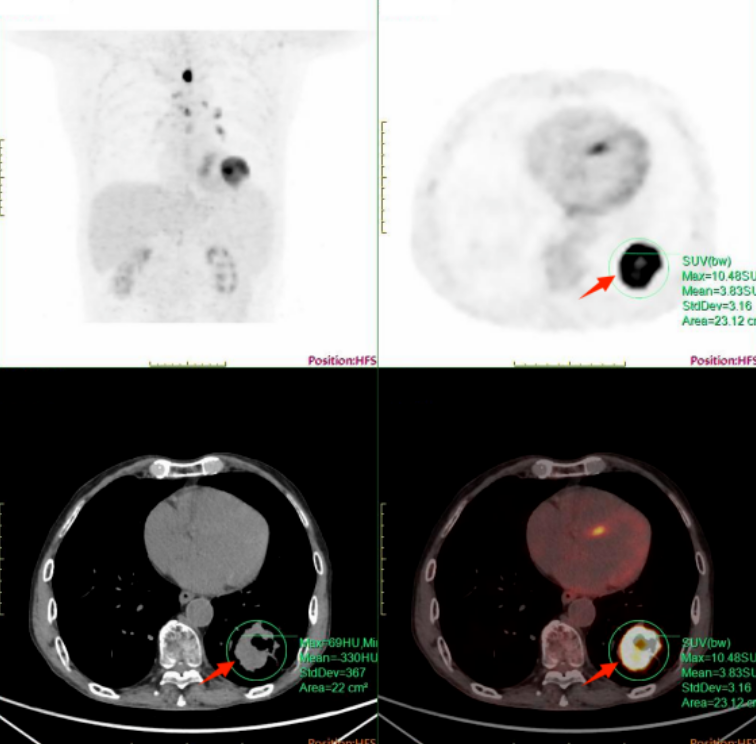

PET-CT影像清晰揭示了多处病灶:左舌根及口咽部不规则肿块符合口咽癌表现,并伴有左颈部淋巴结转移;左肺下叶后基底段新发肿块,代谢增高,考虑为原发性周围型肺癌,并发现左肺门及食管旁淋巴结转移。此次检查通过一次扫描,即实现了对头颈、胸、腹、盆腔的全覆盖,高效明确了口咽、肺部两处原发恶性肿瘤及相关的转移情况。

PET-CT在肿瘤诊疗中的多重临床价值:通过FDG代谢水平准确进行病灶良恶性鉴别;有效区分多原发癌与转移癌,避免治疗方向偏差;全面评估肿瘤侵犯范围与转移状况,为精准分期与制定后续放疗、化疗、靶向或综合治疗方案提供了关键影像学依据。该案例表明,对于具有复杂肿瘤病史的患者,PET-CT可作为实现精准、高效全身评估的重要技术手段。